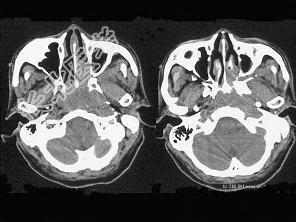

- 单项选择题男,64岁, 间断性流鼻血一年余,近1个月加重, CT如图所示,最可能的诊断为 ( )

A、鼻咽部腺样体增生

B、鼻咽纤维血管瘤

C、鼻咽部恶性淋巴瘤

D、鼻咽部淋巴组织增生

E、鼻咽癌